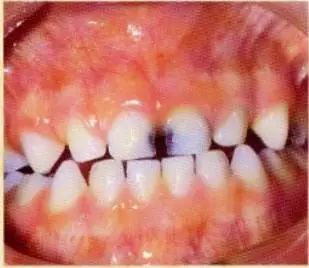

乳牙蛀了,刚开始是这样的。

这只是牙齿小部分变黑,

孩子可能也感觉不到疼。

家长觉得无所谓,不需要补。